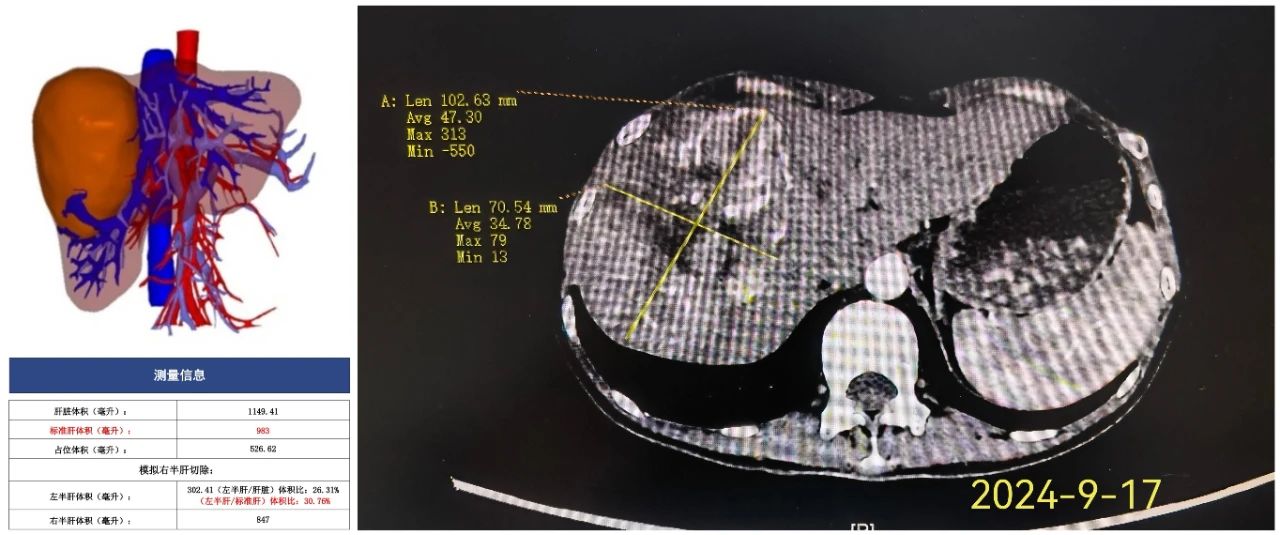

近期,我院肝胆胰外科在陈剑雄主任医师的带领下为一年轻的右肝巨大肝癌患者成功实施了转化治疗。患者苏××,32岁,因“发现肝占位性病变1天”来诊。腹部增强CT检查发现右肝巨块型肝癌,较大截面大小约97mm×72mm×84mm。行三维重建评估剩余肝体积不足30%,无法手术切除。